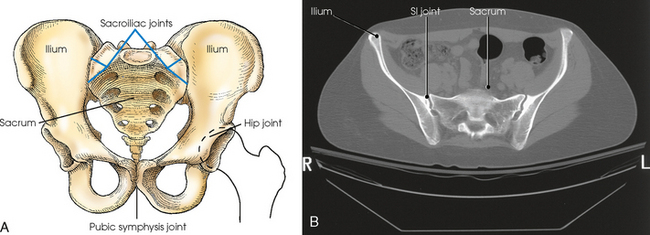

Fig. 7-7 A, Joints of pelvis and upper femora. B, Axial CT image of pelvis showing SI joints. Note 25- to 30-degree angulation of joint. (B, Modified from Kelley L, Petersen CM: Sectional anatomy for imaging professionals, ed 2, St Louis, 2007, Mosby.)

The pubes of the hip bones articulate with each other at the anterior midline of the body, forming a joint called the pubic symphysis. The pubic symphysis is a cartilaginous symphysis joint.

The right and left ilia articulate with the sacrum posteriorly at the sacroiliac (SI) joints. These two joints angle 25 to 30 degrees relative to the midsagittal plane (see Fig. 7-7, B). The SI articulations are synovial irregular gliding joints. Because the bones of the SI joints interlock, movement is limited or nonexistent.